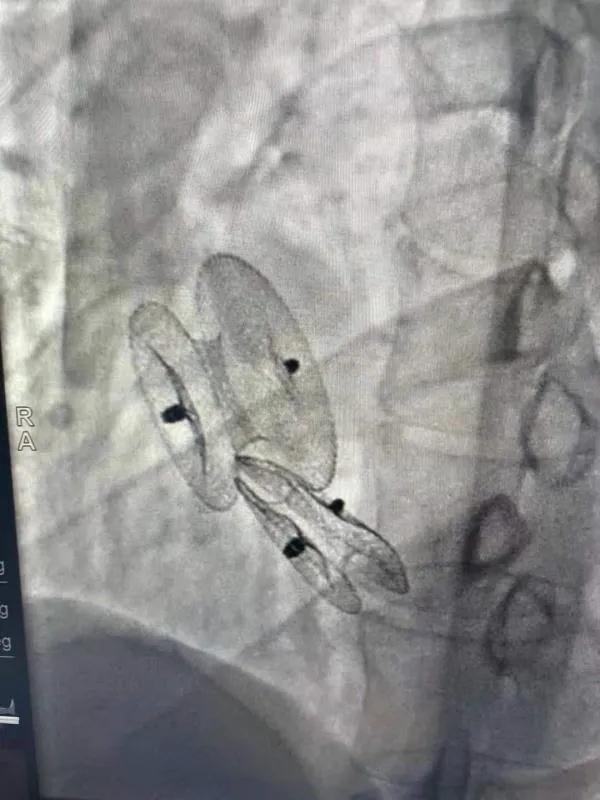

先天性心臟病房間隔缺損呈多孔型怎么辦?患者并非只能選擇開胸手術。近日,西安國際醫(yī)學中心醫(yī)院心臟病醫(yī)院成功開展一例雙孔房間隔缺損雙傘介入封堵術。

房間隔缺損是先天性心臟病的一種,介入手術相較于傳統(tǒng)的外科手術損傷小,風險相對較低,術后恢復快。一般的房間隔缺損多呈單孔,封堵難度較小,而雙孔房間隔的封堵難度大大增加,至今僅有國內(nèi)頂尖的封堵專家成功完成了數(shù)例而已。

患者是位27歲的年輕女性,經(jīng)常感到心慌,心臟超聲發(fā)現(xiàn)房間隔缺損,并且房間隔缺損呈雙孔型,大的約14mm,小的約9mm,兩個缺損間相隔較遠,介入封堵難度非常大。

在詳細了解患者病情,仔細閱讀患者影像資料后,曾廣偉主任已經(jīng)有了清晰的手術策略。在精心的準備和團隊的配合下,曾主任順利的利用兩個封堵器對房缺進行了封堵。